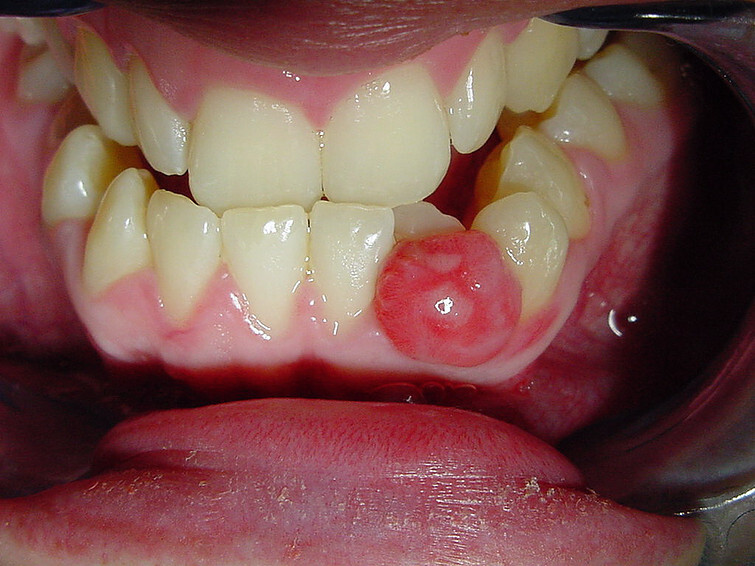

A mouth cyst is a thin, fluid-filled sac on the inside of your mouth. Also known as a mucous cyst or mucocele, the sac will often burst and heal by itself, says Better Health Channel, Victoria. Feeling a bump inside your mouth may annoy you, though.

These cysts commonly occur on the inside of the lips but can also form on your tongue, palate, the inside of the cheeks, the floor of the mouth or around piercings on the tongue. The mucocele sac may be pink or deep blue in colour, or it may be clear if it contains clear fluid. Your dentist can usually diagnose a mucous cyst just by examining it in your mouth.